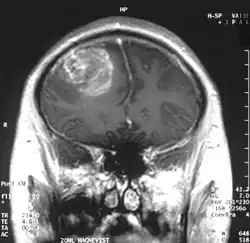

| MRI scan showing a glioblastoma with contrast enhancement | |

Magnetic resonance imaging (MRI) with contrast is the primary imaging modality for diagnosing brain and spinal cord tumors due to its high-resolution visualization of soft tissues. MRI helps identify the tumor's location, size, and potential impact on surrounding structures. In emergency situations or when MRI is contraindicated, a CT scan can be used as an alternative.[12]